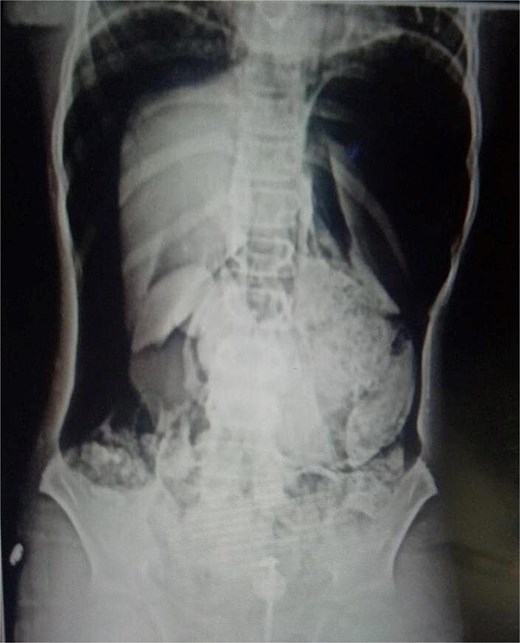

On arrival, he was alert but visibly distressed due to pain. His vital signs were stable initially, but on examination, he had signs of generalized peritonitis with tense, diffusely tender abdomen in all quadrants and absent bowel sounds. Digital rectal examination was unremarkable. Initial laboratory investigations showed a total leukocyte count of 9.3 × 103/μl and platelet count of 143 × 103/μl. A plain abdominal X-ray demonstrated massive pneumoperitoneum (Figs 1 and 2), strongly suggestive of hollow viscus perforation. Based on clinical and radiological findings, a provisional diagnosis of hollow viscus perforation was made.

He underwent emergency laparotomy. A large gush of air upon entering the peritoneal cavity, confirming free intraperitoneal gas, and there was a perforation measuring approximately 3 × 2 cm was identified along the lesser curvature of the stomach, near the incisura angularis (Fig. 3). Primary repair was performed in a double-layer pattern. A drain was placed in the lesser sac to monitor postoperative leakage or bleeding. Postoperatively, he transferred to the High Dependency Unit (HDU) for monitoring. His remaining recovery was uneventful, and he was discharged on day 6.